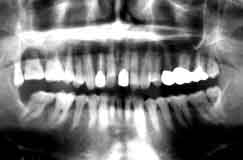

初診時 パノラマ 12年後

数年後が危ぶまれる口腔内状況であった

【症例1】 74歳・男性

喪失歯もなく経過良好

【症例2】 55歳・男性

【症例1】

メインテナンス中の患者さんで、歯周疾患進行は弱いが以前から6|の知覚過敏を訴え ていたが、夜も眠れない程の痛みがあったとのこと。カリエス(-) 最大盲嚢 5mm。

【症例2】

最近初診の患者さんで、歯周疾患進行傾向は並程度であるが、上顎臼歯部の骨吸収が著しく 知覚過敏を訴えている。カリエス(-) 口蓋側の盲嚢は根尖に至る。

【症例1】 は完全な歯髄炎末期症状であったので抜髄、CR充填にて経過良好。

【症例2】 は象牙質知覚過敏状態であったが、直近での歯髄炎は避けられない状況と判断して |6ともども抜髄の上連結固定を予定。

何れの症例もカリエスは全く認められず、歯髄の炎症は象牙質知覚過敏によるものと思われる。 このまま歯髄壊死を放置した場合には、何れも根尖病巣に発展して半年後にはいわゆるエンド・ ペリオとして歯槽骨の全てを失って抜歯になるものと思われる。  そしてその時には、根尖部から歯髄壊死に導く上行性歯髄炎として解釈されるものと思われる。